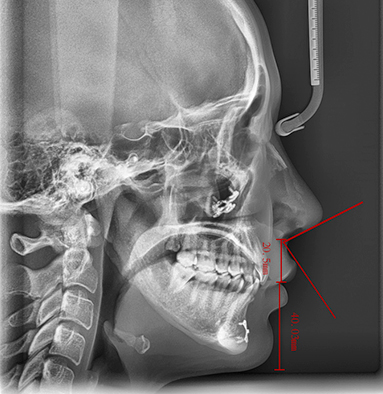

Under the expertise of Dr. Seungil Chung, each patient’s skeletal structure, muscle movement, and lip shape are analyzed in detail to achieve an ideal nasolabial angle and side profile. This is not just a correction—it is a harmonious redesign of the entire face.

Individual skeletal structure, muscle movement, and lip shape are analyzed to achieve the most ideal nasolabial angle and side profile.